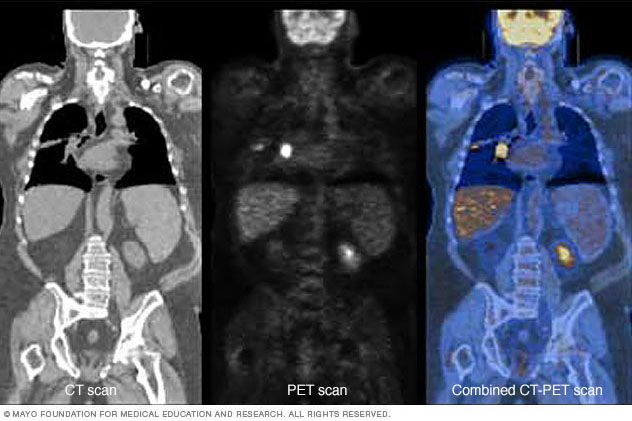

PET plus CT

Combining a PET scan with an MRI or CT scan can help make the images easier to interpret. At left is a CT scan, while the center image is a PET scan. The image on the right is a combined PET-CT scan. The bright spot in the chest, seen best on the PET and PET-CT scans, is lung cancer.